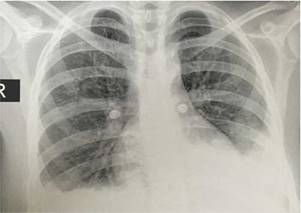

En la radiografía de tórax simple se observó la presencia de derrames pleurales y una imagen sugestiva de consolidación basal izquierda, a pesar de que la paciente no presentaba tos, esputo ni fiebre (fig. 1). En la tomografía simple de tórax se evidenció derrame pleural izquierdo con atelectasia compresiva ipsilateral y bandas parenquimatosas en la base derecha (fig. 2). El ecocardiograma realizado informó de fracción de eyección conservada con una presión sistólica de la arteria pulmonar elevada de 42 mm Hg (Vr. PsAp menor de 36 mm Hg). Se calculó el Systemic Disease Activity Index (SLEDAI) en 21 puntos, considerándose una exacerbación del LES severa. Se inició tratamiento con prednisolona a 30 mg por día, con lo que presentó mejoría de la disnea y de la saturación de oxígeno.

Figura 1 Radiografía de tórax: proyección posteroanterior que evidencia derrames pleurales bilaterales y una imagen sugestiva de consolidación basal izquierda.